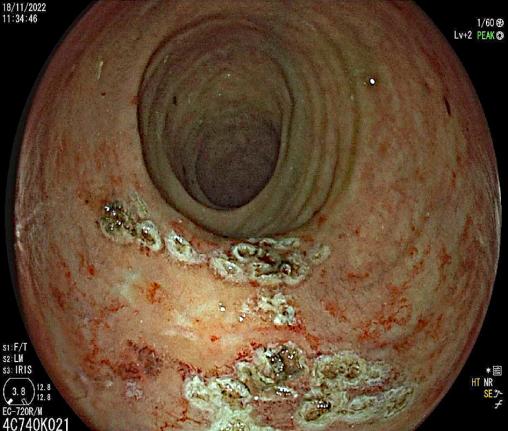

Endoscopie d'une rectite radique chronique hémorragique après traitement des saignements par coagulation au plasma d’argon endoscopique.